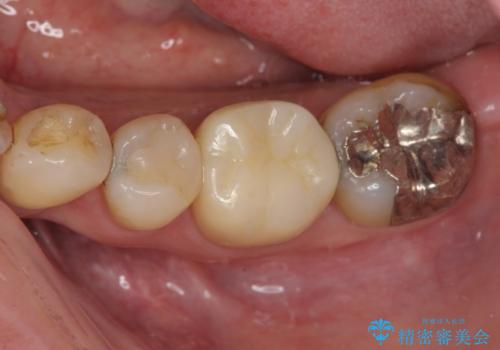

- メタルインレー(保険の金属の詰め物)が取れたとのことで来院された患者様です。

拡大鏡視野下にて、メタルインレーの範囲が大きく虫歯もあったため、オールセラミッククラウンにて修復を行いました。

型どりはシリコーン印象材にて型どりしています。